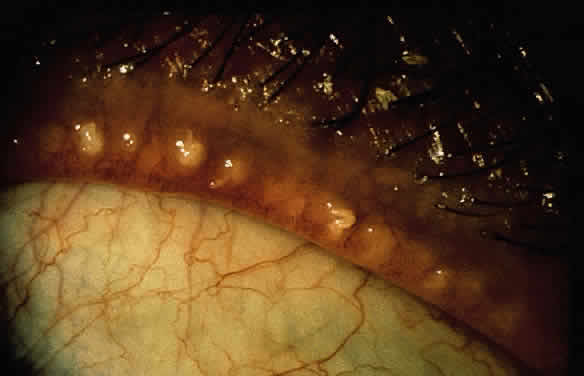

Significant findings include lid-margin inflammation, dry flakes (dandruff) or oily secretion on the eyelashes and lid margins, and concomitant dandruff of the scalp, eyebrows, and external ears (Fig. 1). A mild, fine, medium, or blotchy epithelial keratitis can also occur. Seborrhea is frequently associated with Staphylococcus aureus infections (see later discussion on mixed blepharitis).

Fig. 1. Anterior lid disease probably due to seborrhea with “sleeves” noted along the lashes.